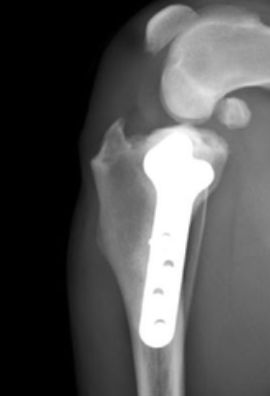

Restore Your Pet’s Comfort and Mobility

We know how hard it is to see your pet in pain. We’re here to help them heal—with skill, compassion, and heart. Our surgical team is here to help. At Pacific Paws, we provide advanced orthopedic surgical solutions designed to get your pet back on their paws.